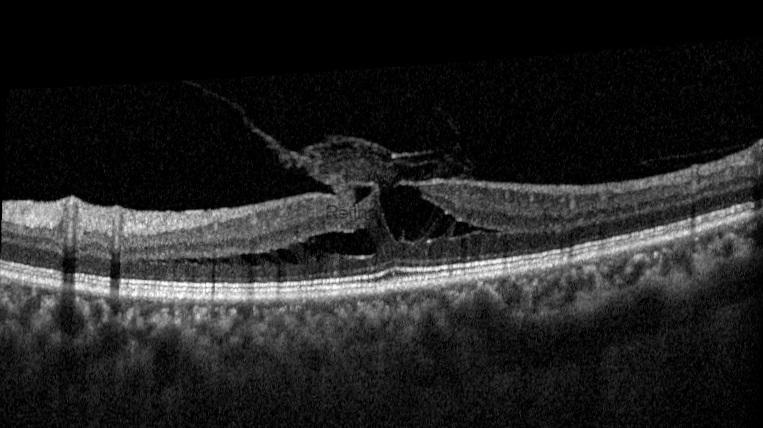

This post will present a Tractional Lamellar Macular Hole surgery. This is a 55-year-old female patient whose left visual acuity has been decreasing over the last 6 months. Her preoperative visual acuity was 20/100. OCT revealed a vitreomacular traction, a Tractional lamellar macular hole (LMH), a thin ERM at the edge of LMH, and a thick fibroglial tissue. The term tractional LMH has recently been changed to ERM-Foveoschisis. However, because the traction of the vitreous and fibroglial tissue on the fovea is the primary concern in this case, it would be more accurate to refer to it by the older term.

Preoperative multicolor image, autofluorescence image, and OCT of the patient with a tractional macular hole